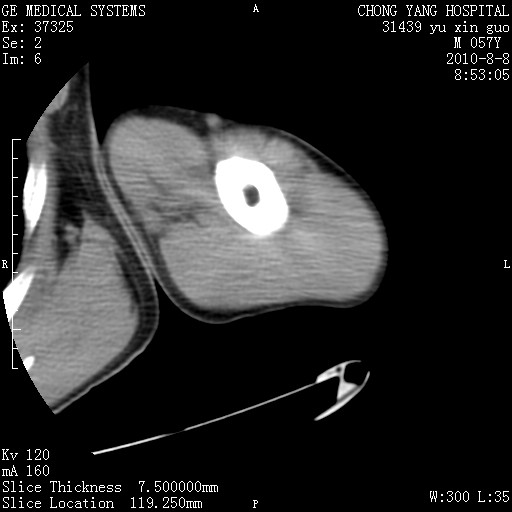

标题: CT28267:M57Y 上臂包块8年余。 [打印本页]

标题: CT28267:M57Y 上臂包块8年余。

典型脂肪瘤改变

包膜光滑、完整的脂肪密度肿块,支持脂肪瘤。

脂肪瘤。有ct值?